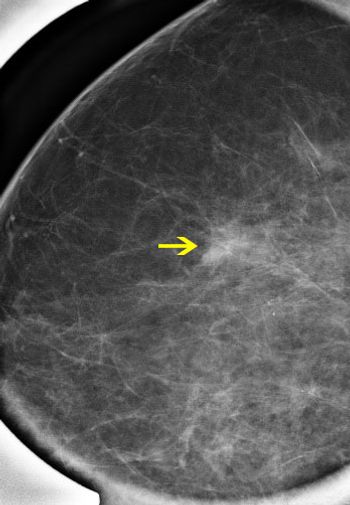

50-year-old patient presented for screening mammogram. Extremely dense breast tissue was noted.